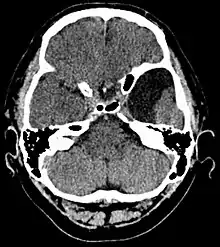

Arachnoid cyst

Arachnoid cysts are cerebrospinal fluid covered by arachnoidal cells and collagen[1] that may develop between the surface of the brain and the cranial base or on the arachnoid membrane, one of the three meningeal layers that cover the brain and the spinal cord.[2] Primary arachnoid cysts are a congenital disorder whereas secondary arachnoid cysts are the result of head injury or trauma.[3] Most cases of primary cysts begin during infancy; however, onset may be delayed until adolescence.[2]

Diagnosis is principally by MRI. Frequently, arachnoid cysts are incidental findings on MRI scans performed for other clinical reasons. In practice, diagnosis of symptomatic arachnoid cysts requires symptoms to be present, and many with the disorder never develop symptoms.